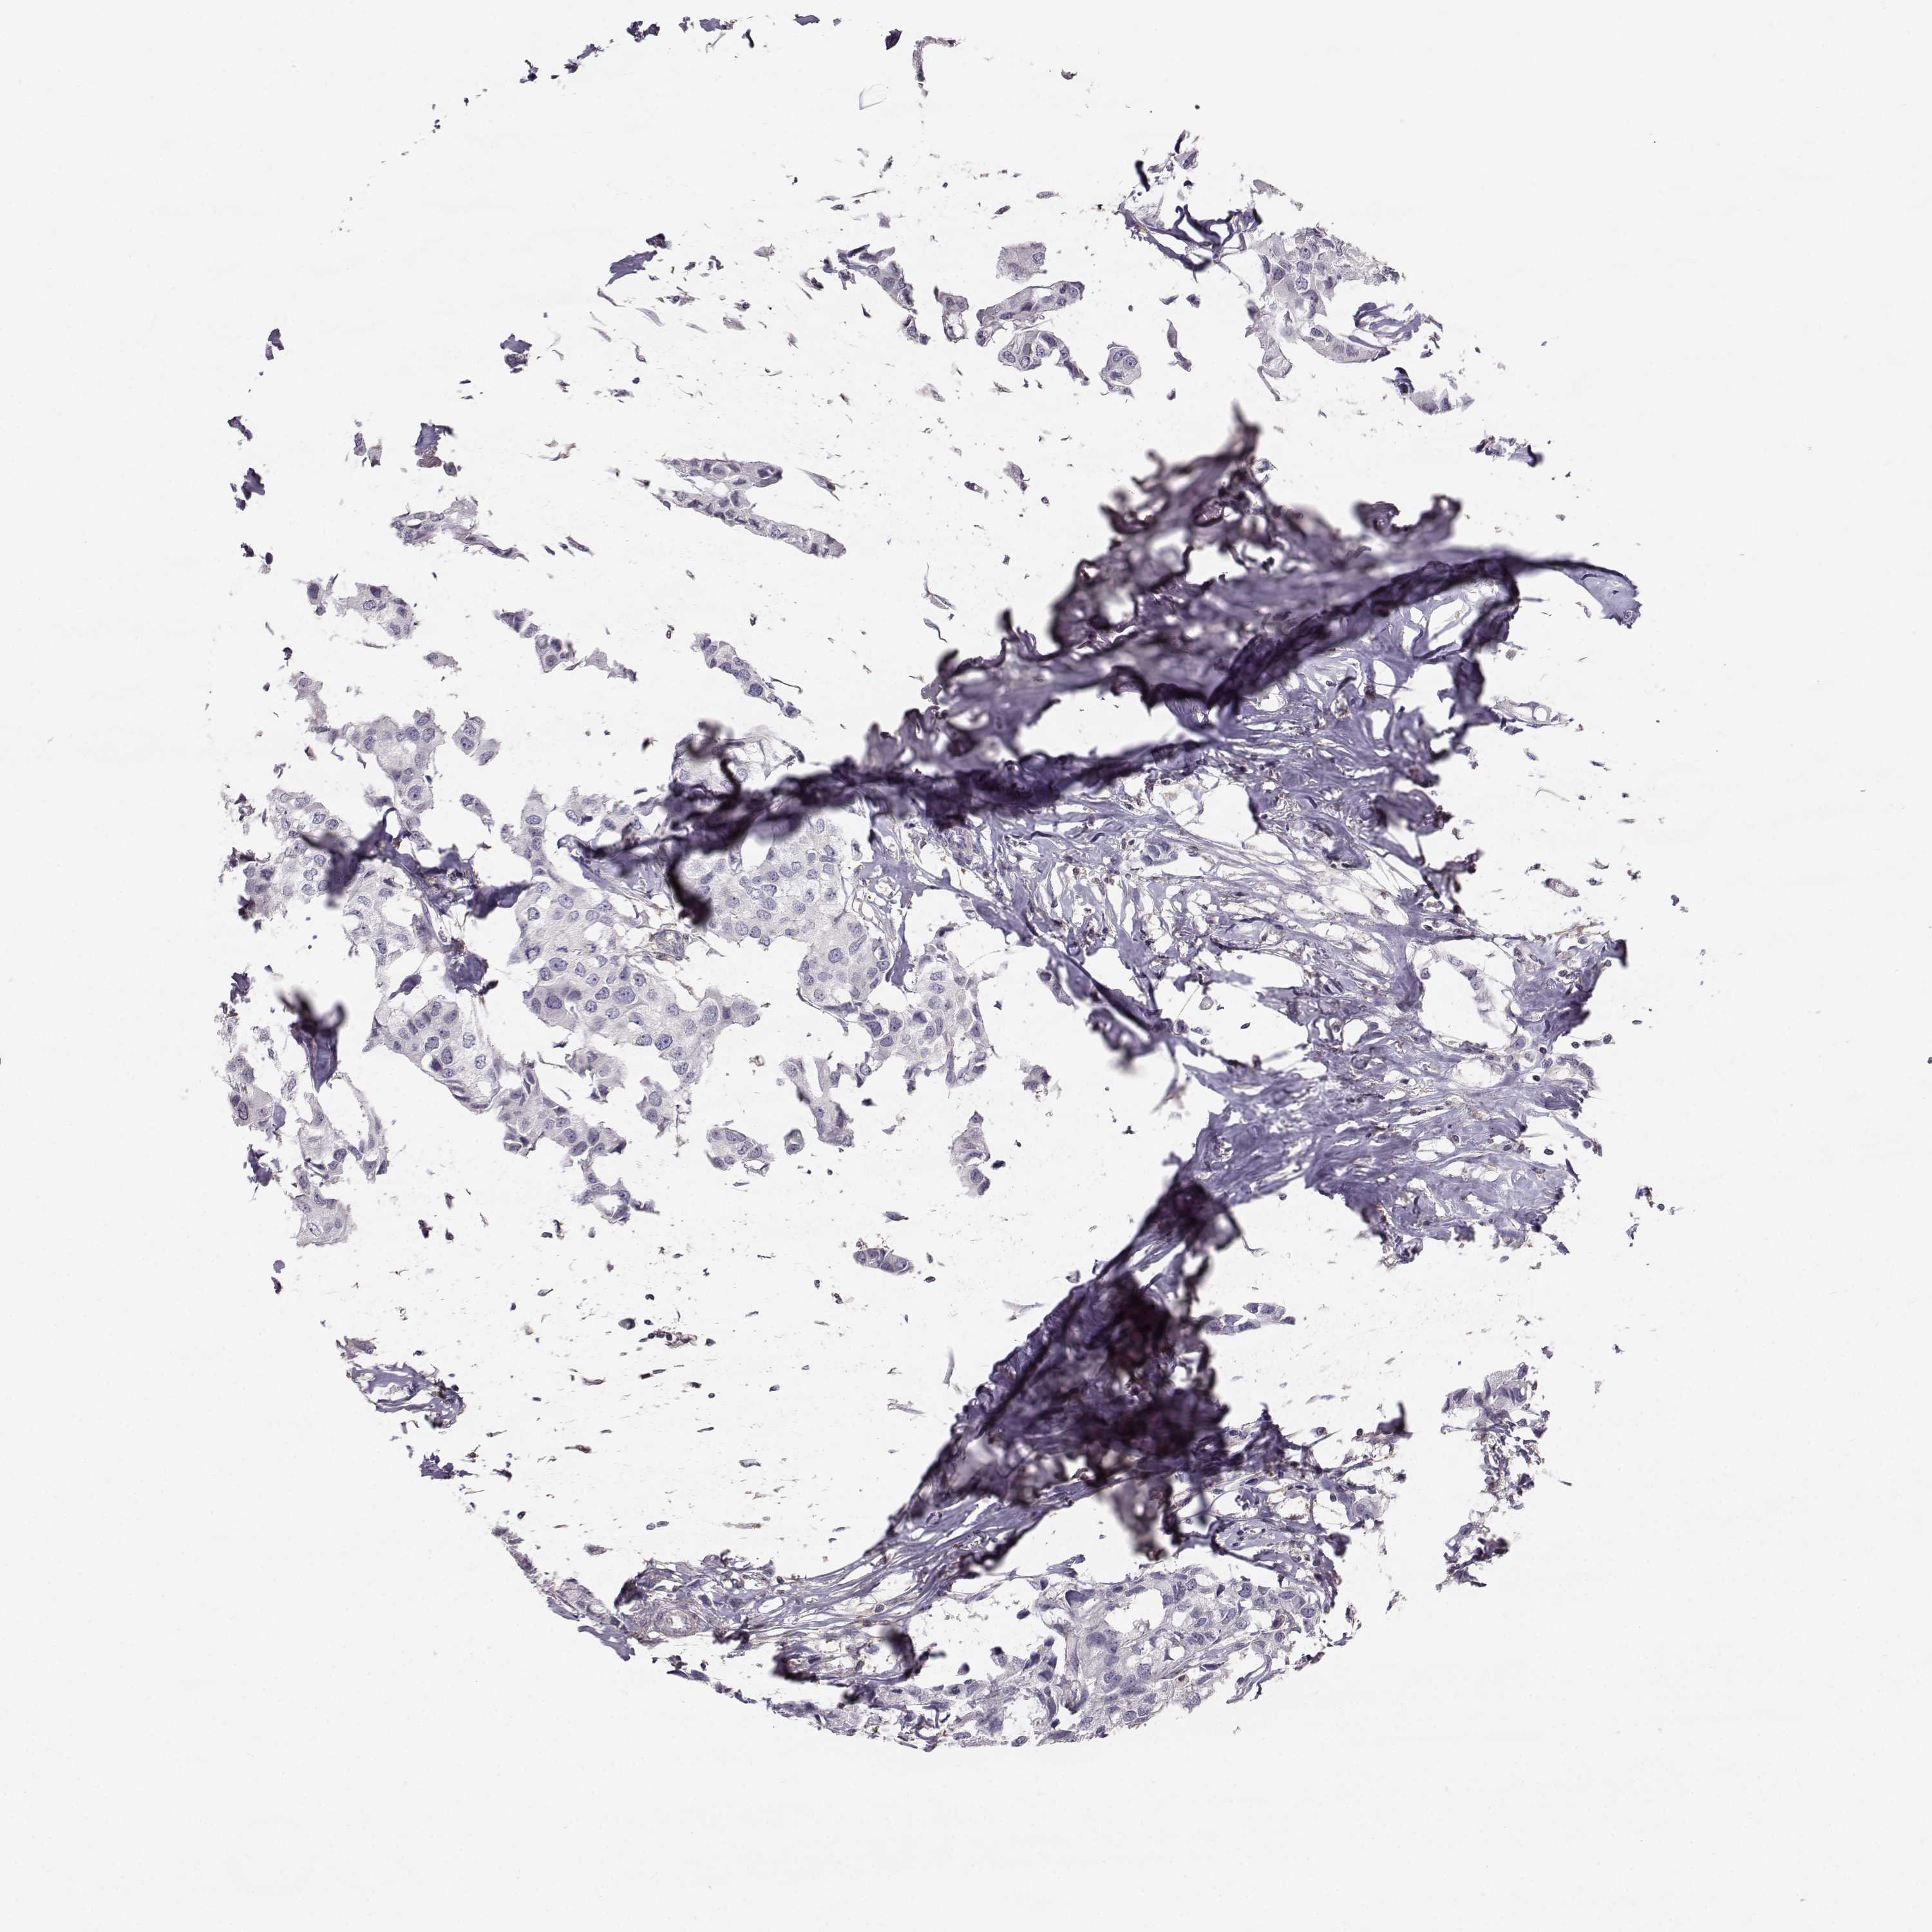

CANCER BREAST CANCER Show tissue menu

BRCA TCGA BRCA VALIDATION PROTEIN EXPRESSION